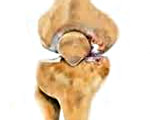

Посттравматический артроз

Посттравматический артроз – это хроническое прогрессирующее поражение сустава, возникшее после его травматического повреждения. Чаще развивается после внутрисуставных переломов, однако может возникать и после травм мягкотканных элементов (связок, менисков...